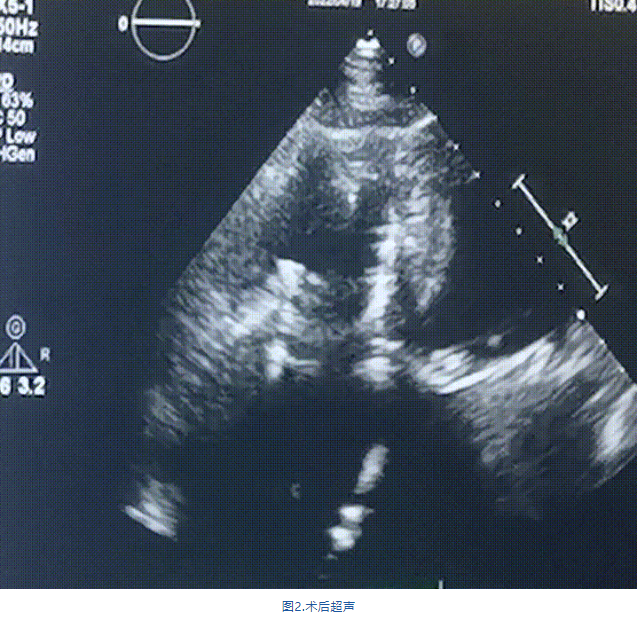

此次手術(shù)在全麻下進(jìn)行,采用經(jīng)右側(cè)頸靜脈入路。術(shù)中在經(jīng)食道超聲和DSA的指引下多個(gè)維度精細(xì)調(diào)整輸送器角度,在達(dá)到正確位置后,逐步釋放瓣膜錨定裝置和盤片,最終完成瓣膜植入。術(shù)后患者右房壓明顯下降,術(shù)后超聲提示人工三尖瓣同軸性良好,瓣架固定牢靠,無反流和瓣周漏,血壓術(shù)后即刻上升20mmHg左右,手術(shù)后監(jiān)護(hù)室順利拔除氣管插管,3天后恢復(fù)良好,予以出院。